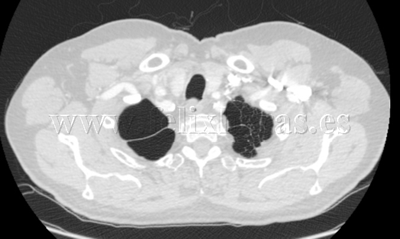

Enfisema pulmonar